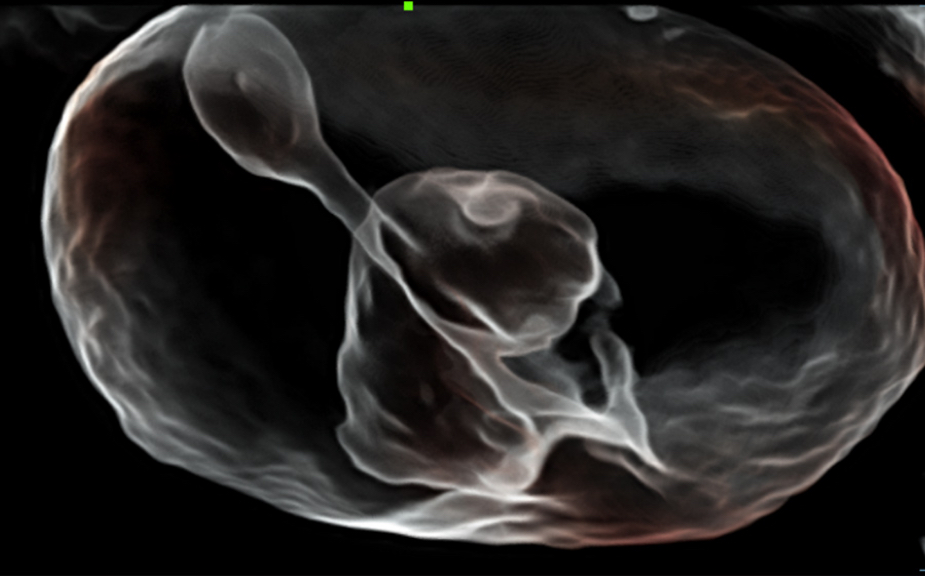

De Nuewa I9, speciaal ontworpen voor vrouwen en neonatale gezondheidszorg, biedt een innovatieve ervaring van binnenuit. Deze innovaties zijn ontwikkeld op basis van diepgaande inzichten in complexe klinische scenario's en bieden nauwkeurige en tijdige antwoorden, evenals een uitstekende effici?ntie en opmerkelijke gebruikerservaring.

Het ZST+ platform is een buitengewone innovatie en revolutie in de wereld van ultrasound. Het transformeert ultrasoundgegevens van conventionele bundelvorming naar kanaalgegevensverwerking. Het overwint de traditionele afweging tussen ruimtelijke resolutie, temporele resolutie en weefseluniformiteit, en levert een uitzonderlijke beeldkwaliteit voor oneindige beeldvormingsoplossingen met non-stop verbeteringen.